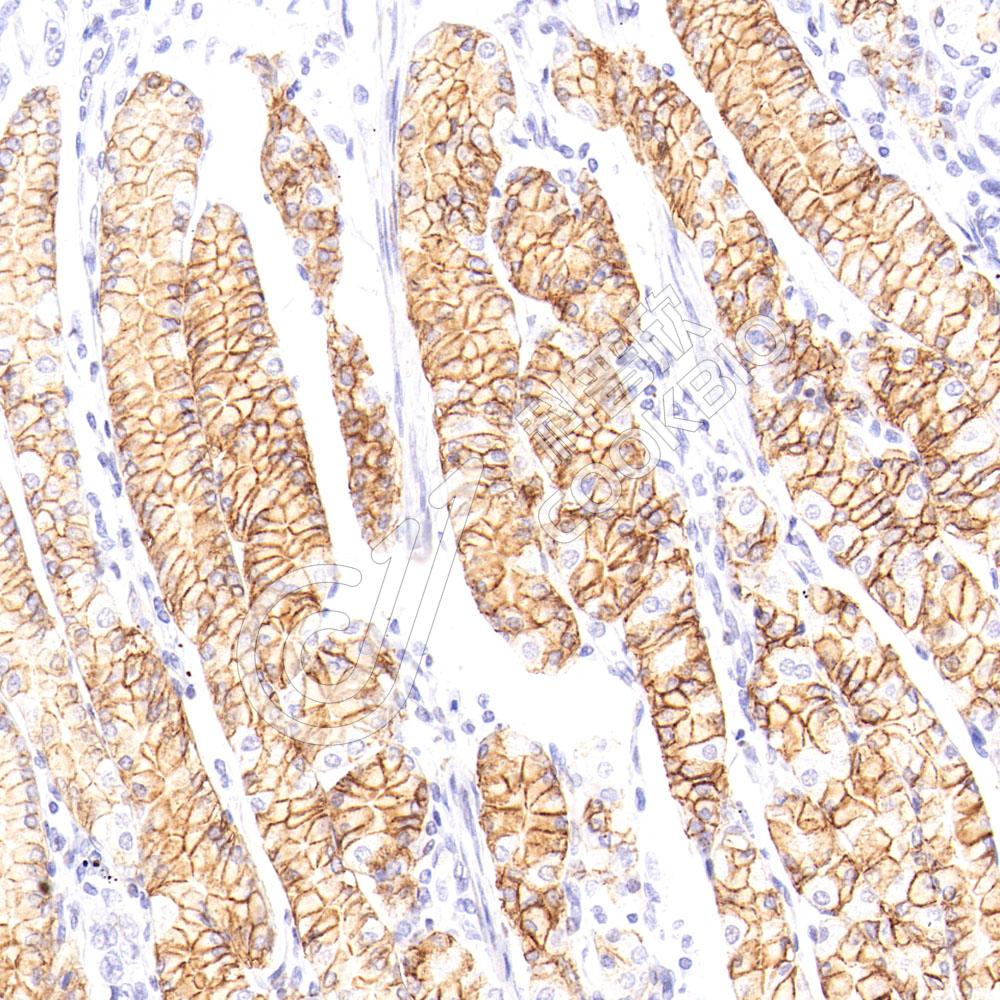

IHC检测Carbonic Anhydrase 9/CA9蛋白(货号 K2363552).

样品: 人胃癌, 4%多聚甲醛 (货号KSG1101) 固定12-24小时.

抗原修复: 柠檬酸抗原修复液(干粉, pH 6.0) (KSG1201), 高压锅均匀喷气计时2分钟.

—抗: 1: 1000稀释, 4℃ 孵育过夜.

二抗: S-vision免疫组化多聚二抗(山羊抗小鼠), 即用型(货号KB3903), 室温孵育20分钟.